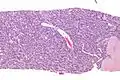

| Micrograph of an adenomyoepithelioma. H&E stain. | |

The histomorphologic appearance can mimic invasive ductal carcinoma, the most common type of invasive breast cancer.